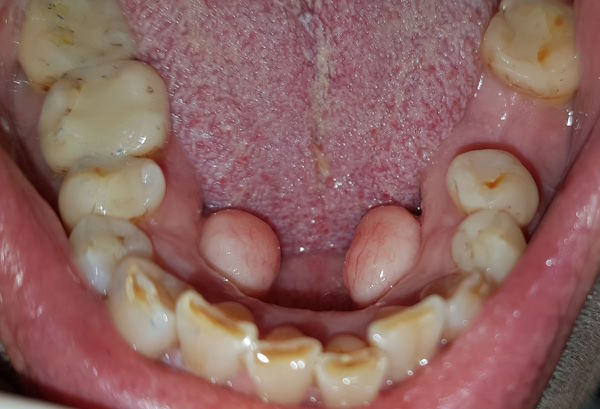

15-jähriger Patient (20.01.2016 / 4868)

Dieser Weisheitszahn gehört einem jungen Mann aus Süditalien. Er ist erst 15 Jahre und 5 Monate alt und hat bereits drei durchgebrochene Weisheitszähne - und hat sie ohne Schmerzen bekommen!

Hintergrund: Die normale Durchbruchszeit von Weisheitszähnen lag um 1970 im Kanton Zürich zwischen 18 und 22 Jahren. Offenbar kann das Wachstum auch viel rascher sein. Möglicherweise bekamen unsere Vorfahren in der Eiszeit ihre Weisheitszähne auch so früh und problemlos.